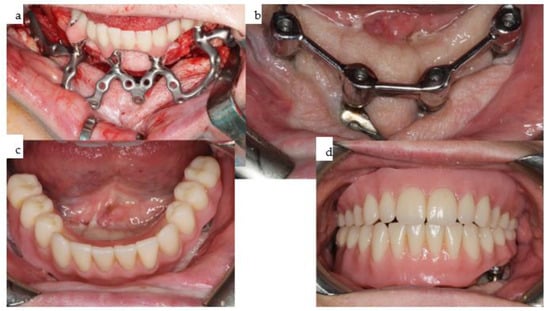

Figure 9. (ad): Four intraoral views showcase the healthy tissues surrounding the four posts of the one-piece subperiosteal IPS Implants® Preprosthetic (KLS Martin-Group, Tuttlingen, Germany). A bar-retained overdenture is utilized for both the maxilla and mandible (ac), with the hard palate left uncovered. The maxillary bar is screw-retained on the four posts (a,b), while in the mandible, the bar is screw-retained on the three secondarily inserted implant abutments and telescoped onto the two previously placed implants placed elsewhere (d).